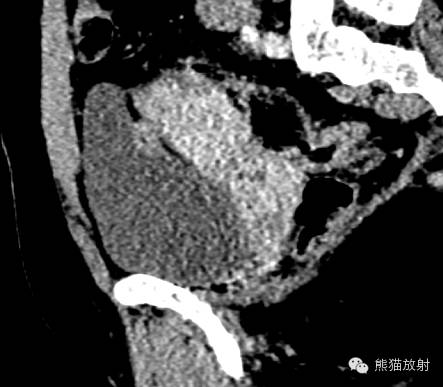

女,33岁,2年余前在月经期时,出现尿频、尿急,伴全程肉眼血尿,呈淡红色,无血块,有时可有尿痛;经期结束后,上述症状消失。

膀胱镜检查:膀胱三角区及各壁粘膜可见充血炎性改变,三角区后方可见一范围约1.5×2cm的粘膜隆起,局部可见紫蓝色的粘膜下瘀斑,于该处取病理2;

活检病理示:(膀胱)送检少许组织被覆尿路上皮,呈轻度慢性炎,间质中查见少数散在的腺体,结合临床和免疫表型,符合子宫内膜异位;免疫组化:ER 、PR 、CD10-、CK34βE12±、CK7±。

膀胱子宫内膜异位症

膀胱内异症 病理图(来自文献)

诸病灶分别如下图中圆圈所示: